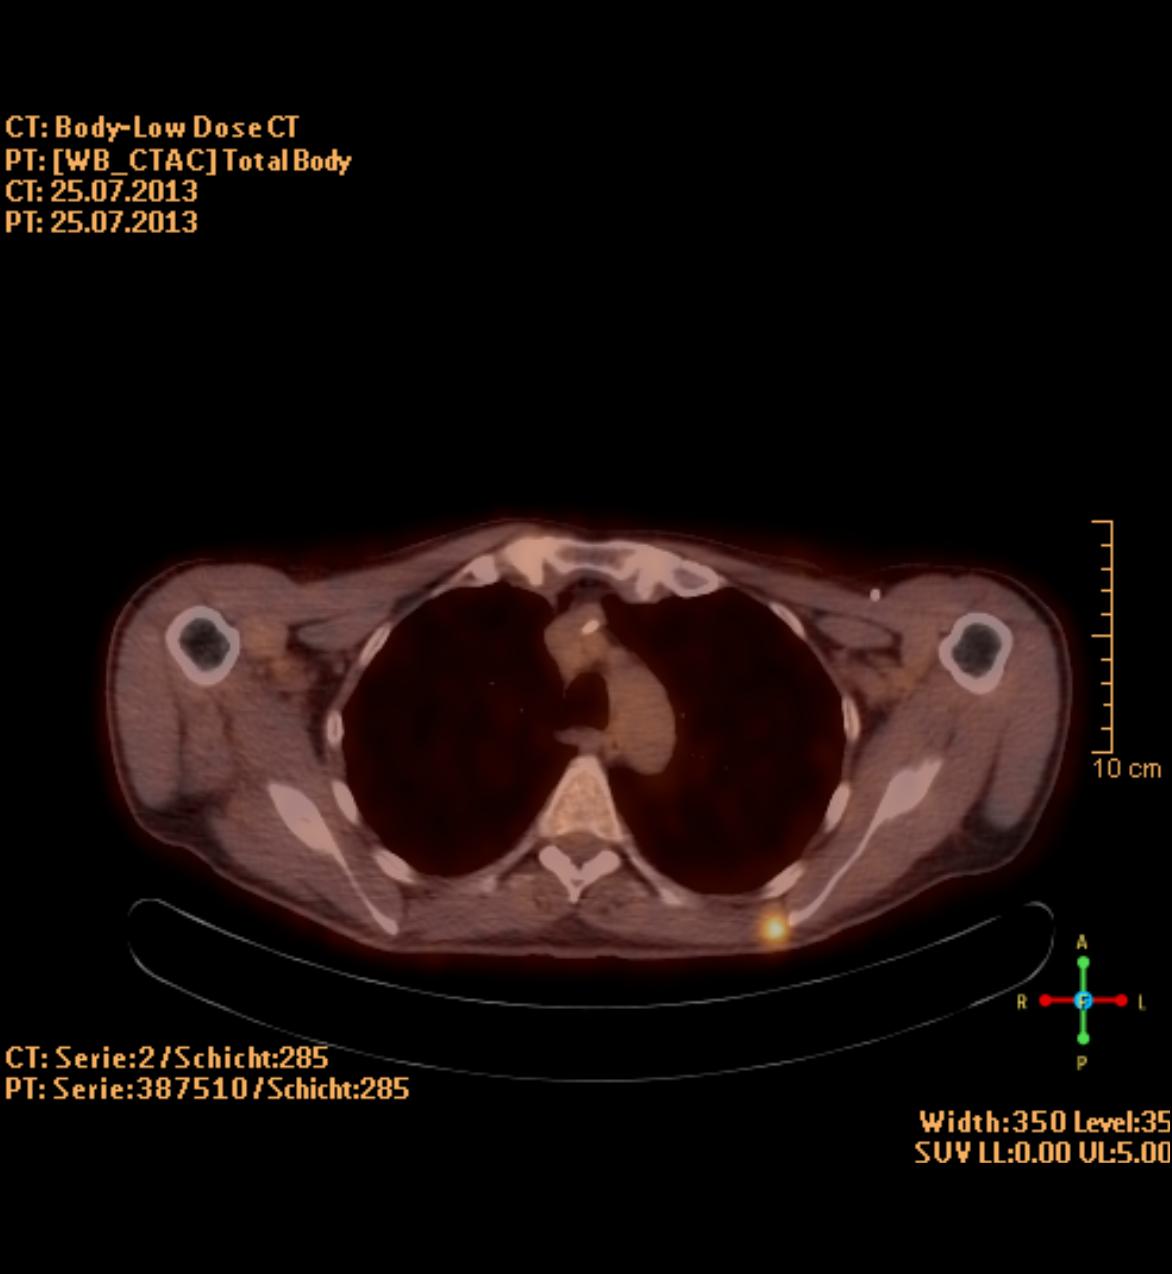

Die PET/CT ist in der Medizin derzeit die modernste zur Verfügung stehende bildgebende Untersuchung in der Diagnostik von Tumorleiden. Sie ermöglicht oft, sehr kleine Herde früher als mit anderen Verfahren wie Kernspintomographie (MRT) oder alleiniger Computertomographie (CT) zu entdecken. Ein besonderer Vorteil des Verfahrens besteht in der Kombination zweier bildgebender Verfahren, die sich perfekt ergänzen. Durch die CT Technik können Körperregionen und mittlerweile auch der gesamte Körper als vollständiger, lückenloser Datensatz erfasst werden. Dadurch entstehen Bilder in bis dahin ungeahnter Schnelligkeit und Qualität. Im PET werden im Gegensatz zum CT in erster Linie funktionelle Stoffwechselvorgänge im Körper dargestellt. Dazu wird Ihnen radioaktiv markierter Zucker (Glucose) in minimaler Menge in eine Vene injiziert. Die Verteilung im Körper wird mit einer speziellen Kamera (PET/CT-Scanner) gemessen, die Schnittbilder des Körpers gewinnt.

Die Glucose wird mit dem Radionuklid Fluor-18 markiert, das eine Halbwertzeit von 110 min hat. Das bedeutet, dass alle 2 Stunden die Radioaktivität um die Hälfte abnimmt. Zusätzlich wird innerhalb der ersten 2 Stunden ein Großteil der Radioaktivität über den Urin ausgeschieden. Insgesamt ergibt sich daraus eine durchschnittliche Strahlenbelastung von 6 mSv. Durch die PET wird also das Doppelte der natürlichen jährlichen Strahlenbelastung verursacht.

Zusammen mit der PET wird in der gleichen Untersuchung eine Computertomographie (CT) durchgeführt. Je nach Fragestellung und wenn schon Voraufnahmen vorhanden sind, wird das CT meist als Niedrig-Dosis CT ohne Röntgenkontrastmittel gefahren, d.h. mit niedriger Strahlenbelastung aber eingeschränkter Erkennbarkeit von anatomischen Details.

Ein Hybridgerät zwischen PET und CT in 64-Zeilen Technik wie am Klinikum Ludwigshafen kombiniert also in idealer Weise die detailgerechte hoch ortsaufgelöste Abbildung morphologischer und funktioneller Krankheitsaspekte insbesondere im Bereich der Onkologie.